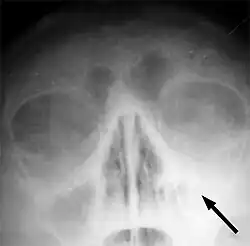

![]() RTG snímek v semiaxiální projekci - sinusitida levé čelistní (maxilární) dutiny. Na snímku je patrné zastření levé (tedy na pravé straně snímku ležící) dutiny podmíněné nahromaděním tekutiny | |

- RTG snímek hlavy v několika projekcích představuje základní vyšetřovací metodu